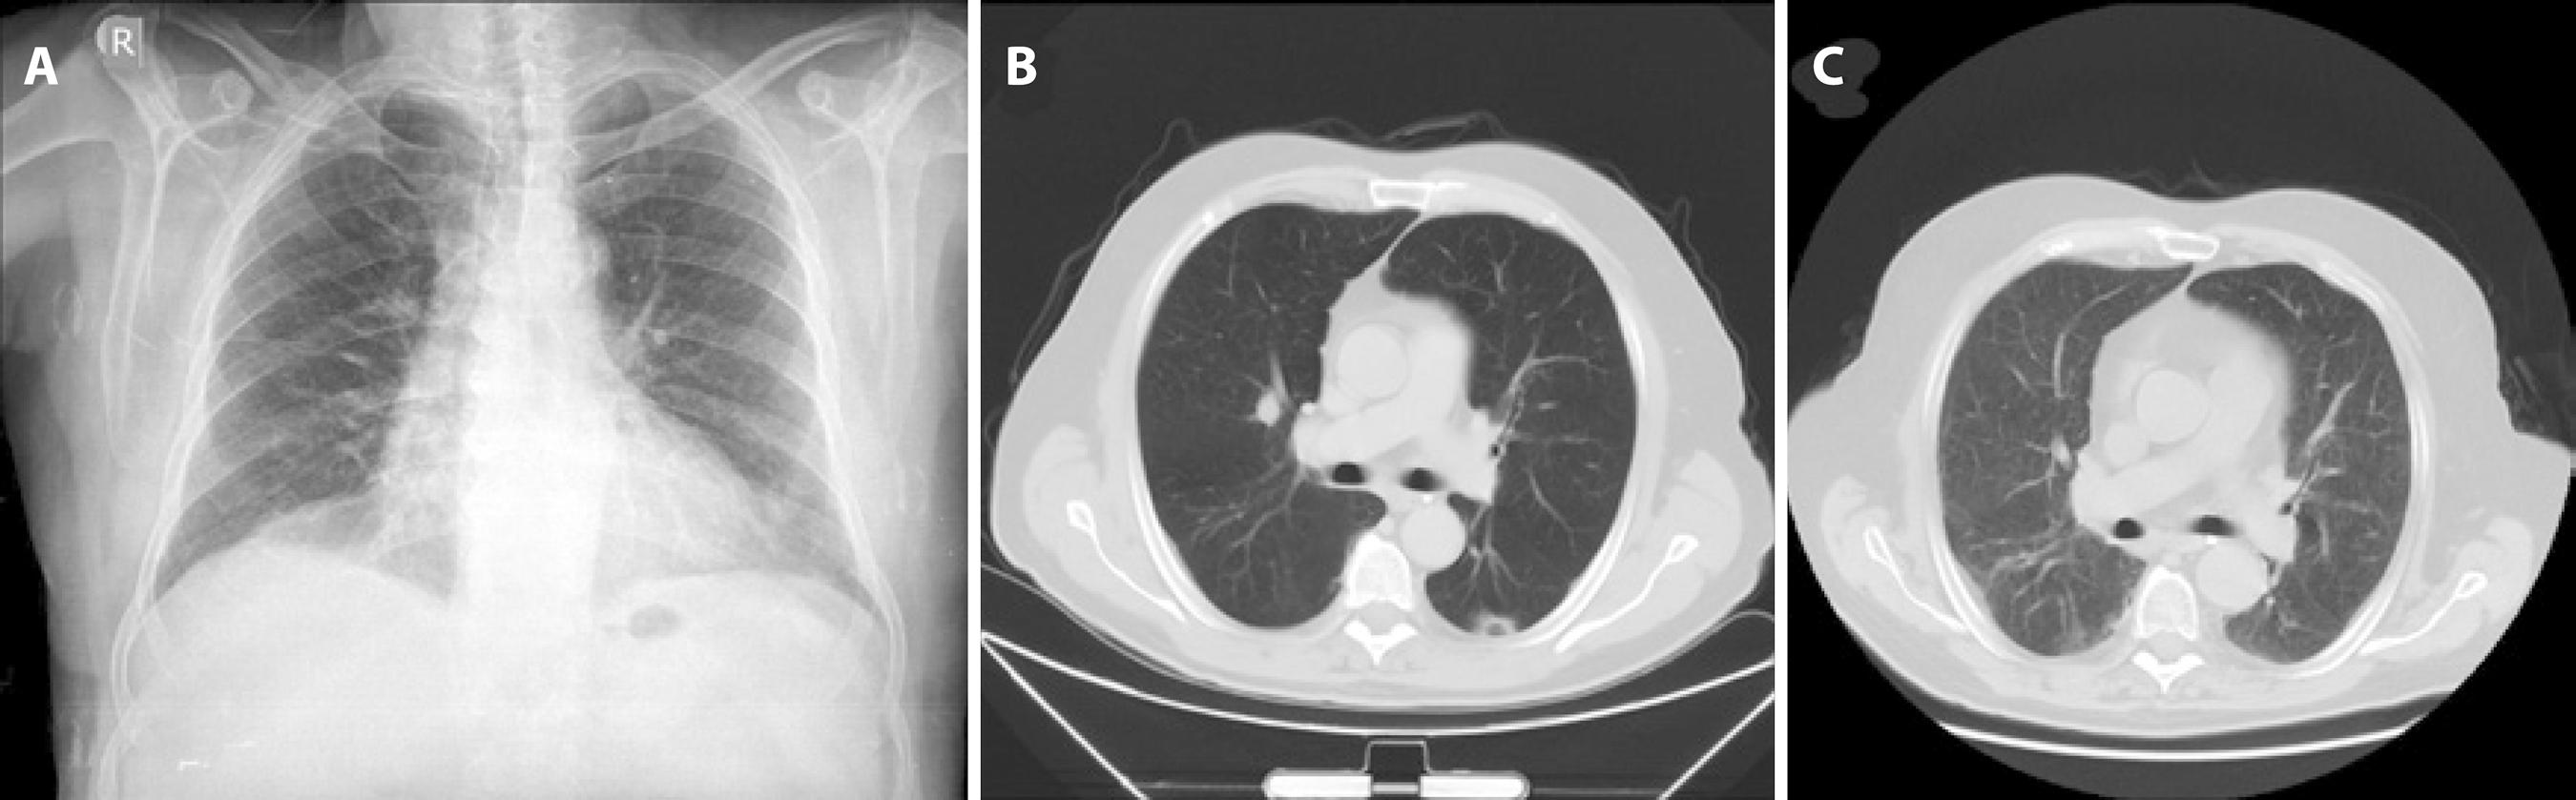

The patient reported a one-week duration of shortness of breath and mild fever at the initial presentation. We therefore arranged a consultation with our department of respiratory medicine on the first day of hospitalization. Laboratory examinations and radiological evaluations were planned by the same department. Serological examination demonstrated an elevated erythrocyte sedimentation rate, proteinuria, and elevated levels of C-reactive protein, urea, and creatinine. Chest radiography and computed tomography (CT) revealed ground glass opacities with nodular consolidation in the right upper lobe. Enlarged bilateral axillary, paratracheal, and carinal lymph nodes were also noted (Figure 2 A, B). Subsequently, he was evaluated by our departments of rheumatology and nephrology. Abdominal CT and ultrasonography revealed bilateral cysts within the kidney parenchyma. Pathological examination of a kidney biopsy specimen was reported as consistent with focal and segmental glomerulosclerosis (FSGS) with chronic tubulointerstitial changes. Additional laboratory evaluations revealed the presence of autoantibodies to neutrophil cytoplasmic components (cytoplasmic anti-neutrophil cytoplasmic antibodies, C-ANCA) with proteinase-3 (PR3) specificity. Granulomatosis with polyangiitis (Wegener's) was diagnosed accordingly and treatment with cyclophosphamide and prednisolone was initiated.

Figure 2 A) Chest radiography revealed bilateral opacities consistent with focal consolidation. B) Chest CT demonstrated ground glass opacities with focal regions of consolidation in the right upper lobe. C) Chest CT at 3 months after systemic cyclophosphamide and prednisolone therapy demonstrated complete resolution of nodular opacities in the right upper lobe.

The patient attended a follow-up visit one week later and reported complete resolution of his ocular symptoms. His BCVA had improved to 20/20 and 20/25 in the right and left eye, respectively. IOPs were 15 mmHg in the right eye and 16 mmHg in the left eye. Openings created by laser iridotomy were seen to be patent. Gonioscopy revealed angles open to the scleral spur bilaterally. All systemic symptoms continued to gradually improve with systemic treatment (Figure 2 C).